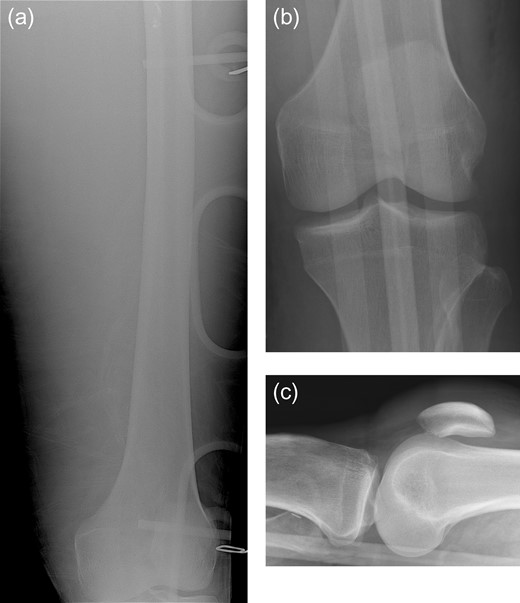

A 29-year-old male presented to the trauma center following a MCC. The Glasgow Coma Score was 5 at the scene, requiring immediate intubation. The systolic blood pressure was 98/50 mmHg, and the heart rate was 120 beats per minute. On physical examination, breath sounds were decreased to auscultation on the left, and a left chest wall deformity was noted. The left lower extremity was swollen and tense, and distal left lower extremity pulses were absent. A chest tube was inserted into the left hemithorax. Intravenous fluids and blood were administered, achieving only a transient improvement in vital signs. A focused assessment with sonography for trauma was negative. Radiographs of the left femur and left knee (Fig. 1a–c) demonstrated no evidence of fracture or dislocation. Due to continued hemodynamic instability and clinical evidence of left lower extremity compartment syndrome, the patient was taken emergently to the operating room.

Portable frontal view of the left femur (a) obtained in the trauma bay demonstrates no evidence of acute fracture. Subsequent AP (b) and cross-table lateral (c) radiographs of the left knee demonstrate no evidence of acute fracture or dislocation.